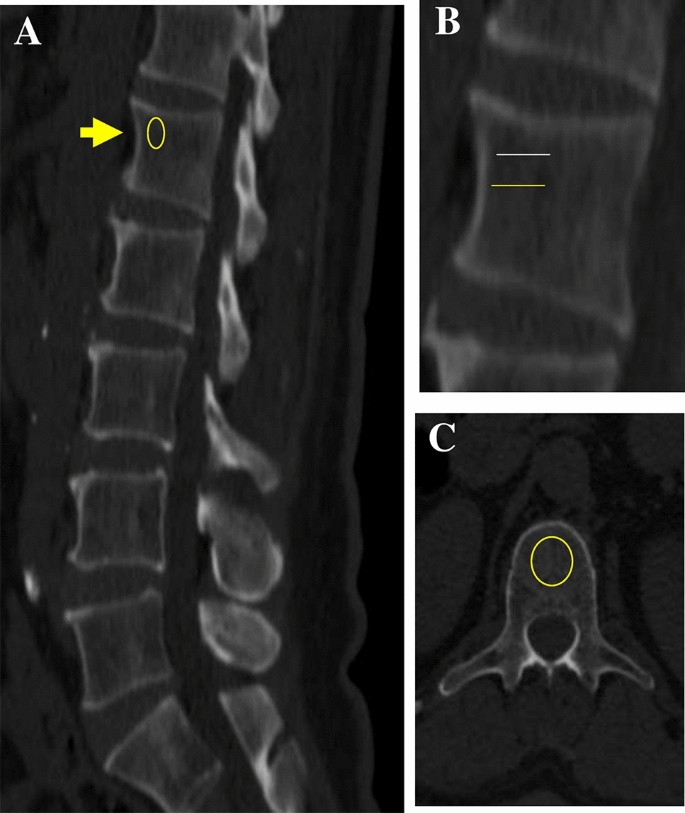

We used 1-mm thick abdominal sections from CT examinations, obtained during ambulatory or emergency room visits, using a Siemens SOMATOM Definition AS + Scanner (Siemens Healthcare GmbH, Erlangen Germany) or a Philips Brilliance ICT scanner (Haifa, Israel). We retrospectively accessed the CT examinations at a constant peak voltage of 120 kV with a variable mAs tube. We included CT scans with or without a contrast agent (n = 76 no-OSA and n = 90 OSA), and evaluated vertebral BMD on a standard radiology picture archiving and communication (PACS) system workstation, with images viewed in bone windows, i.e., gray-scale assignment of the image display, to emphasize bone without the influence of alteration/BMD values (Fig. 3)16,48. We included examinations either with or without an intravenous enhancement agent. We assessed vertebral BMD by placing a single oval click-and-drag region of interest (ROI) in an axial and sagittal slice over an area of vertebral body trabecular bone and then measured CT alteration in HU, with lower HU (lower alteration) representing less-dense bone, at each of the T12 and L1 levels. On the axial images of the selected slice—the superior part of the vertebra—the elliptical ROI was encompassed manually as the largest possible area at the anterior portion of each vertebral body, and in the sagittal plane, we focused on the upper anterior part of the vertebra in order to avoid the Dense Tracecular zone. The mean CT scan density of the ROI was measured. We avoided placing the ROI near areas that would distort the BMD measurement (focal heterogeneity or lesion, posterior venous plexus, compression fracture, and artifacts). The two CT scans of each participant were performed under similar settings, and a CHS engineer from the Biomedical Engineering Department calibrated the CT scanners routinely according to the manufacturer’s instructions using an American College of Radiology-accredited phantom. BMD was expressed in milligrams per milliliter of hydroxyapatite16.

Example of unenhanced computed tomography (CT) images of the spine of a 59-year-old woman. (A) Bone window showing the first lumbar vertebra level (arrow) and oval yellow ring shows the ROI, (B) Magnified view of the first lumbar vertebra and region of interest. The yellow midline line matches the automated level; the white line reflects the standard manual level. (C) First lumbar vertebra axial image; oval yellow ring shows the region of interest. CT examination was performed at a constant peak voltage of 120 kV.